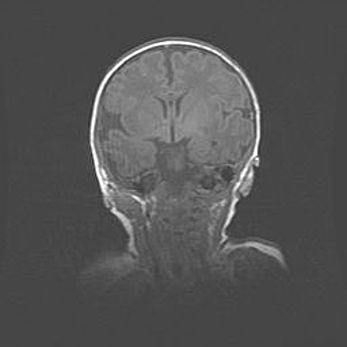

Церебральная ишемия II.

Возраст: 7 дней

Вес: 3350 г

Пол: женский

Окружность головы: 35 см

Срок гестации: 39 недель

Ишемия головного мозга – это состояние, которое развивается в ответ на кислородное голодание вследствие недостаточного мозгового кровообращения. У новорожденных она является следствием дефицита кислорода, что ведет к метаболическим расстройствам различной степени тяжести в тканях головного мозга, в том числе к развитию коагуляционных некрозов и гибели нейронов.